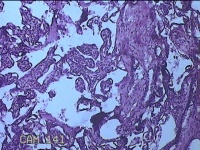

胎盘组织

性别

女

年龄

35岁

临床诊断

胎膜早破 早产

一般病史

停经36周,阴道流液3天。

标本名称

大体所见

灰白暗红色胎盘组织18x15.5x2.3㎝一个,表面光滑,血管清晰,颜色发暗,绒毛面结节状,轻度糜烂,表面有少许凝血块,切面见绒毛内有部分淤血,边缘蜕膜可见多个小血肿,脐带15x1.5x0.8㎝,切断脐带,见脐血管内有凝血块。